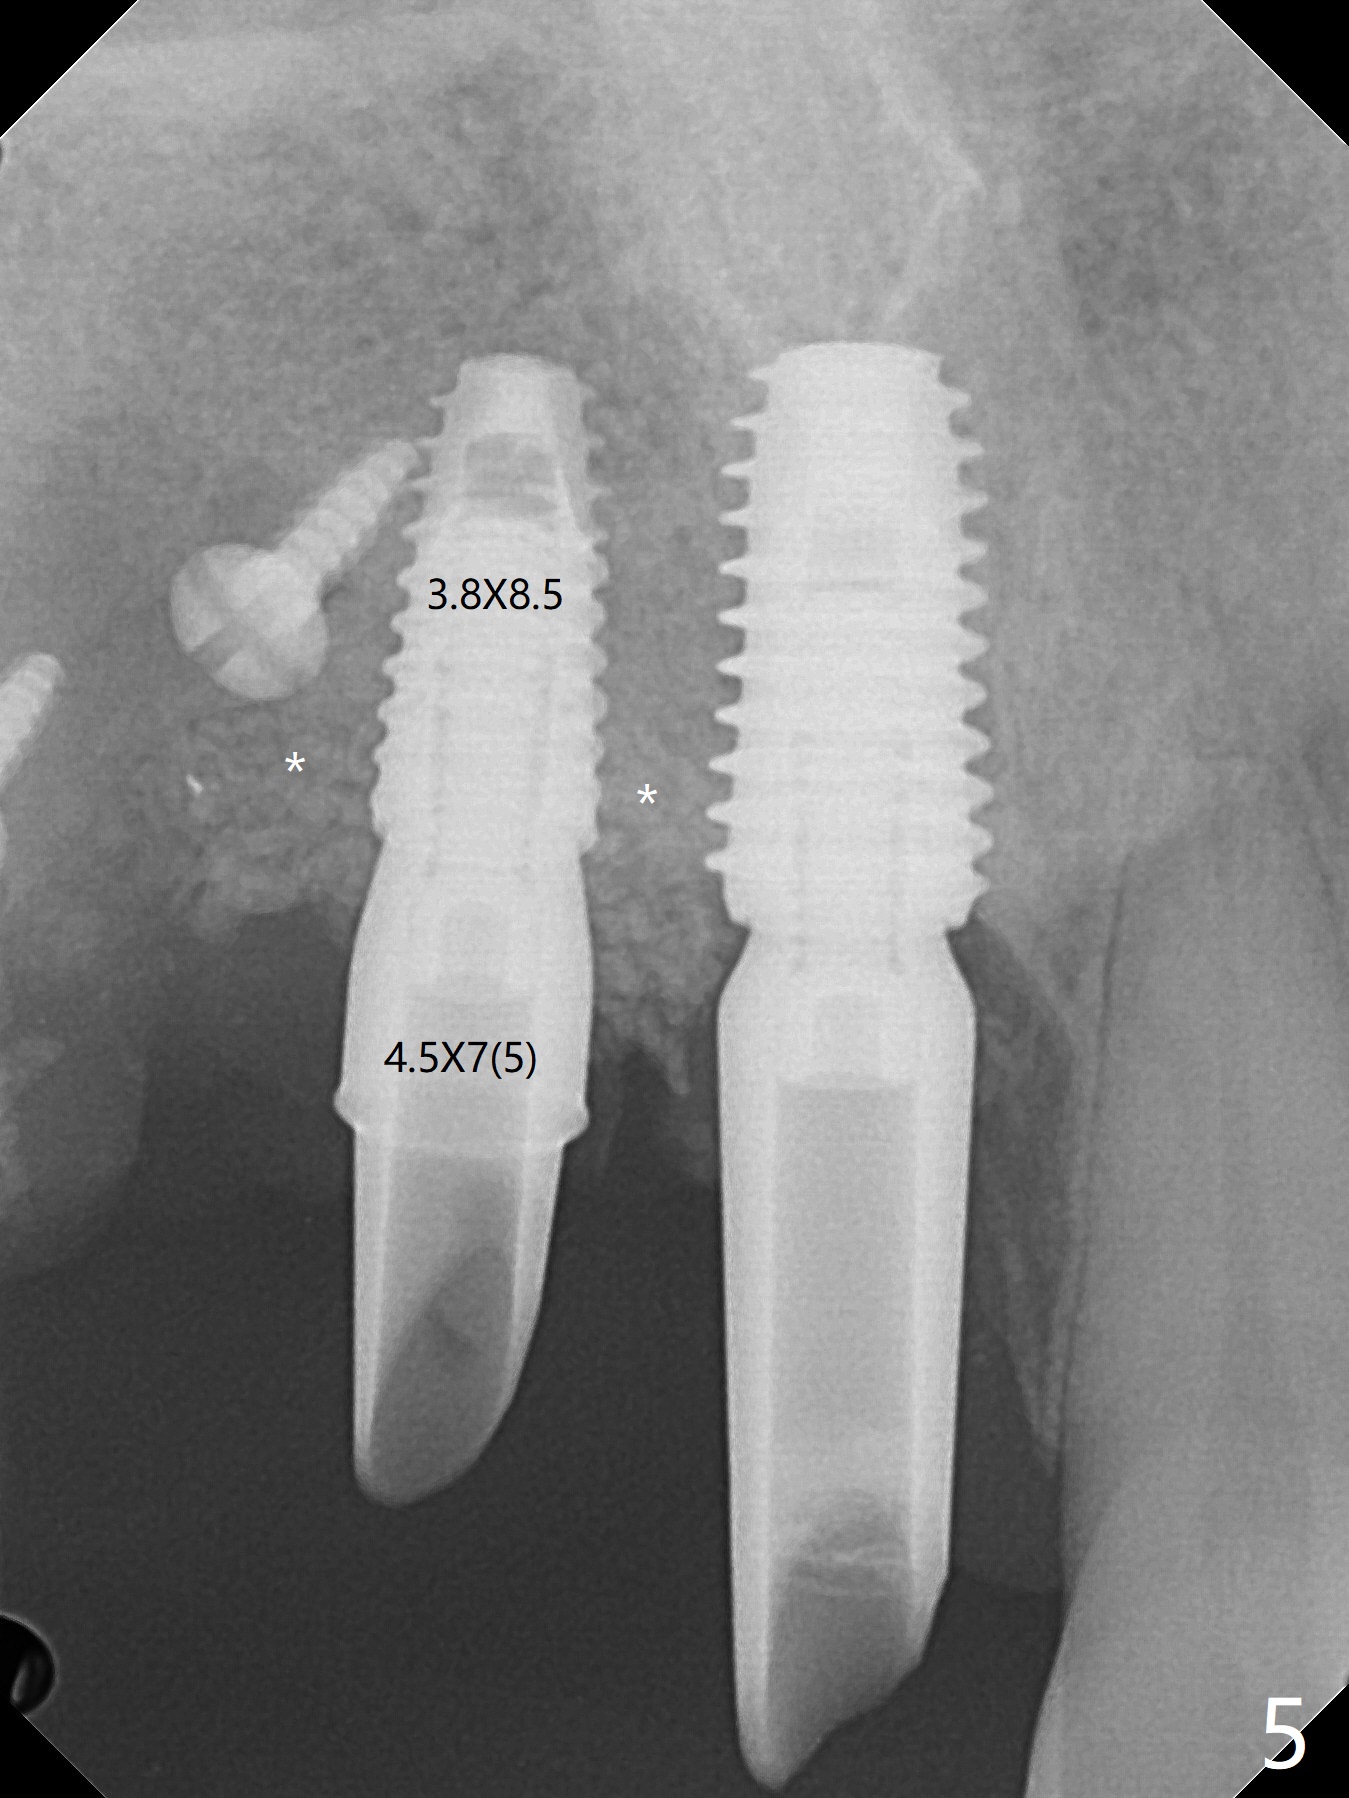

在6,7号牙位牙槽嵴切口,翻瓣,找不到上次放置的tenting screw,不过7号牙位骨质虽然低,够宽的,开始钻洞(图四),植入3.8乘8.5毫米植体,扭力足够(图五),近中舌侧暴露螺纹堆加骨粉(图五*),然后放置基台,再次在后者周围放置骨粉(图五至七),覆盖两张PRF膜后缝合(图八),最后在三个箭头周围放置牙周敷料。术后CT显示植体与tenting screws(图九,十箭头)有一定距离,但是5号牙植体颊侧根尖穿孔(图九 *)。如果植体不脱落,需做侧方切口植骨。术后七天7号植体腭侧肿胀(图十一 *),切开没有脓水,插入牙胶尖,它末端指向7号植体周围tenting screw。后者可能需要拔除,同时5号牙颊侧根尖植骨,但是为时太早,可能打搅骨粉生长。术后两周腭侧肿胀没有消失,但是不痛,继续观察。术后接近6个月,软组织正常(图十三),但是5,7植体周围没有骨质(图十四,五)。由于近中tenting screws周围软组织触痛(局麻不全情况下),螺钉取出(图十六,七(*)),而远中螺钉好像有帮助5植体螺纹骨粉撑起,所以留下(腭侧穿孔部分去除),最后放置粘性骨粉(图十八:*)和PRF膜(两张由7基台打孔固定)。